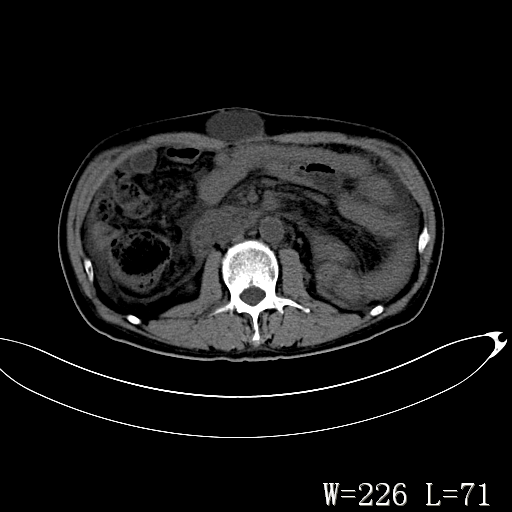

男,52岁,门脉高压断流术后1年,发现腹部肿物2月。

1)前腹壁中线区(脐上方)囊性占位性病变,考虑淋巴囊肿。2)腹水。